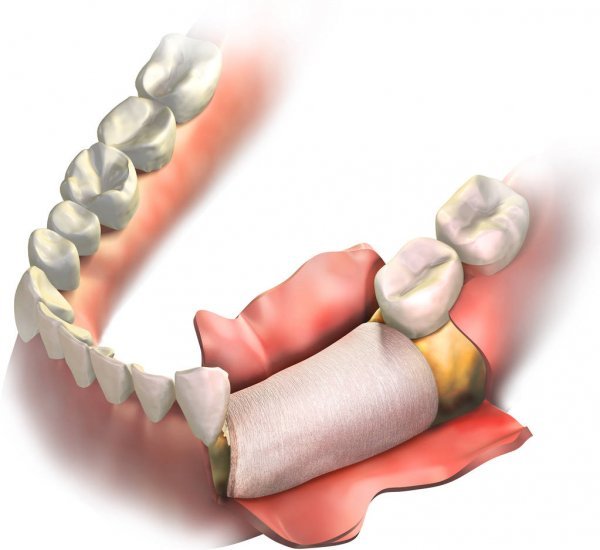

Este procedimiento permite reconstruir y fortalecer el hueso para que el implante tenga una base sólida, segura y estable.

Es un procedimiento que consiste en regenerar o aumentar el hueso en zonas donde se ha perdido, con el objetivo de crear una base adecuada para la colocación de un implante.

Con anestesia local y técnicas avanzadas, realizamos el injerto óseo en la zona en donde se colocará el implante.

Durante el procedimiento buscamos:

Regenerar hueso perdido

Crear una base firme

Evitar movilidad del biomaterial

Preservar estética y función

Reducir molestias al mínimo

Dependiendo del caso, el injerto puede colocarse:

Antes del implante (injerto previo)

El mismo día del implante (colocación simultánea)